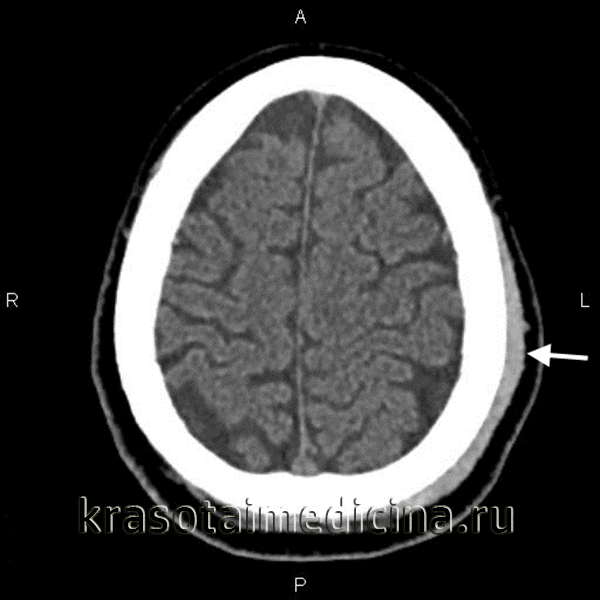

Современные методы нейровизуализации позволяют не только диагностировать внутримозговую гематому, но и выявить причину ее появления. Ведущим диагностическим методом являются:

- КТ головного мозга. Как правило, на томограммах внутримозговая гематома имеет вид очага гомогенной плотности округлой или овальной формы. Если гематома сформировалась в результате ушиба головного мозга, то она обычно имеет неровный контур. С течением времени происходит уменьшение плотности гематомы до изоплотного состояния, при котором ее плотность соответствует плотности мозговой ткани. Для малых гематом этот период составляет 2-3 недели, а для средних — до 5 недель.

- МРТ головного мозга. При уменьшении плотности гематома лучше визуализируется при помощи МРТ, хотя в начальном периоде применение МРТ может привести к ошибочному диагнозу в пользу опухоли с кровоизлиянием. Поэтому, при наличие такой возможности, многие неврологи и нейрохирурги предпочитают использовать в ходе диагностики оба способа нейровизуализации (КТ и МРТ).

- Церебральная ангиография. С целью выявления сосудистых нарушений, обусловленных рефлекторным ангиоспазмом, а также для диагностики аневризм и артерио-венозных мальформаций применяется ангиография головного мозга или магнитно-резонансная ангиография (МРА). Самостоятельно применяться в диагностике внутримозговой гематомы ангиография не может, поскольку не дает возможности точно отдифференцировать участок ушиба головного мозга от гематомы.

Дифференцировать внутримозговую гематому следует с опухолью полушарий мозга, очагом ушиба мозга, ишемическим инсультом, кистой и абсцессом головного мозга.